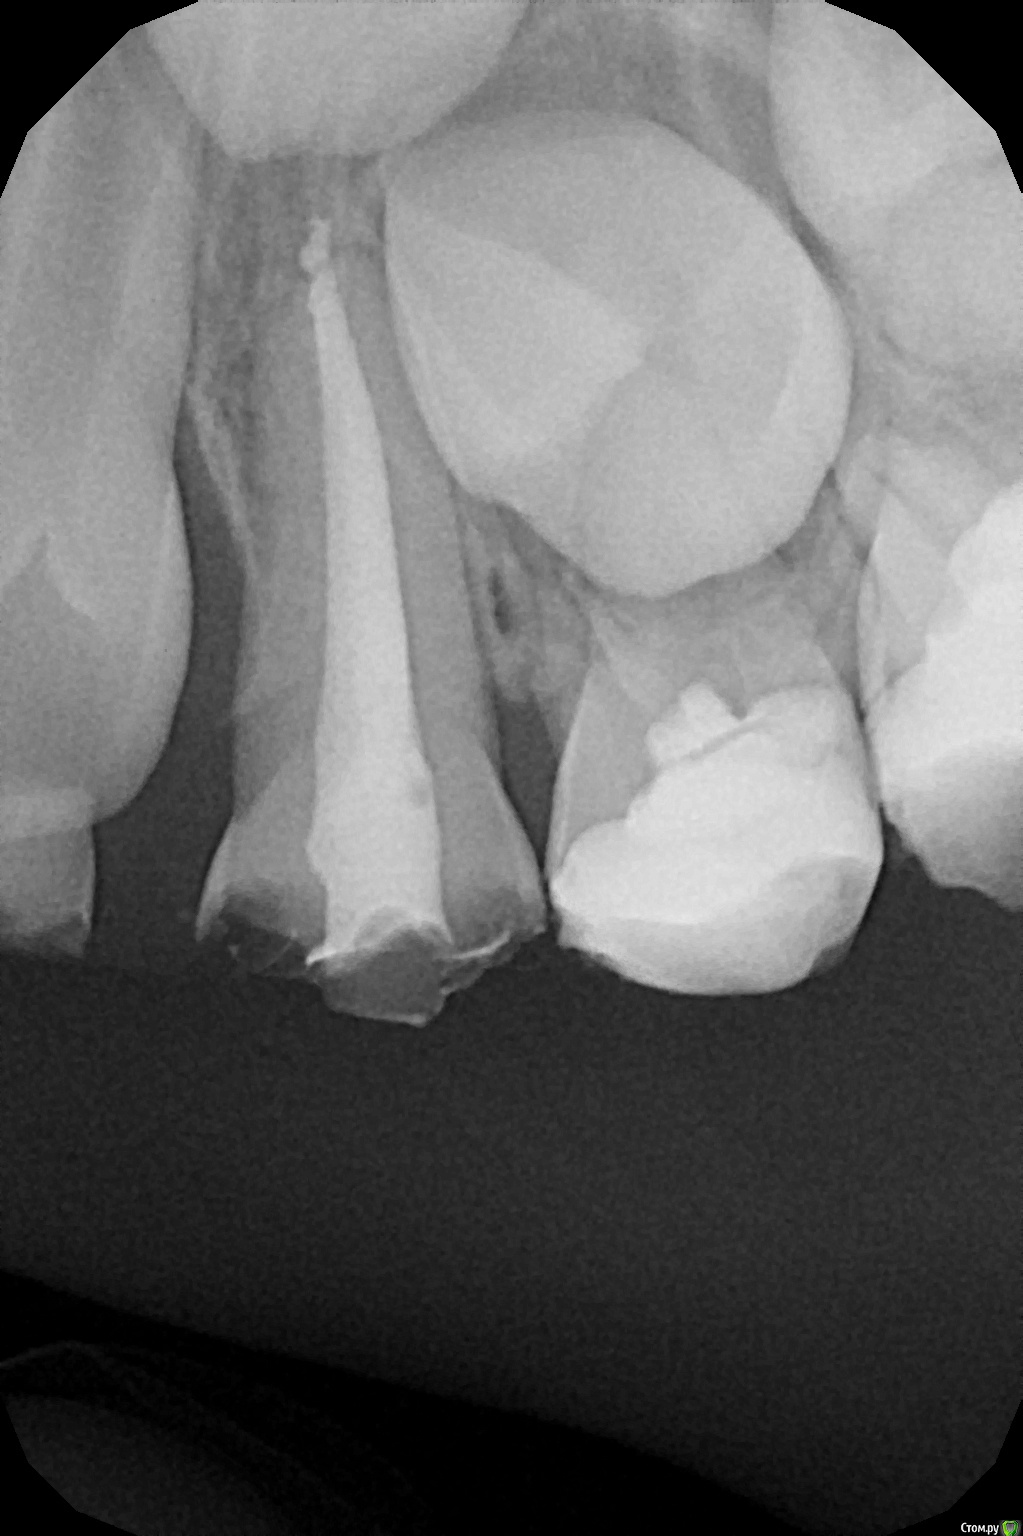

crown Опубликовано 9 июля, 2016 Поделиться Опубликовано 9 июля, 2016 Не знаю имел ли смысл поиск МБ2 и ДБ2, ну вообщем все 5 каналов в сборе) Правда ушло много времени и ребенок очень устал, что повлияло на качество обтурации. 3 Ссылка на комментарий

crown Опубликовано 10 июля, 2016 Поделиться Опубликовано 10 июля, 2016 А чем пломбировали?цоэ, метапекс думаю за 5 лет рассосется. Ссылка на комментарий